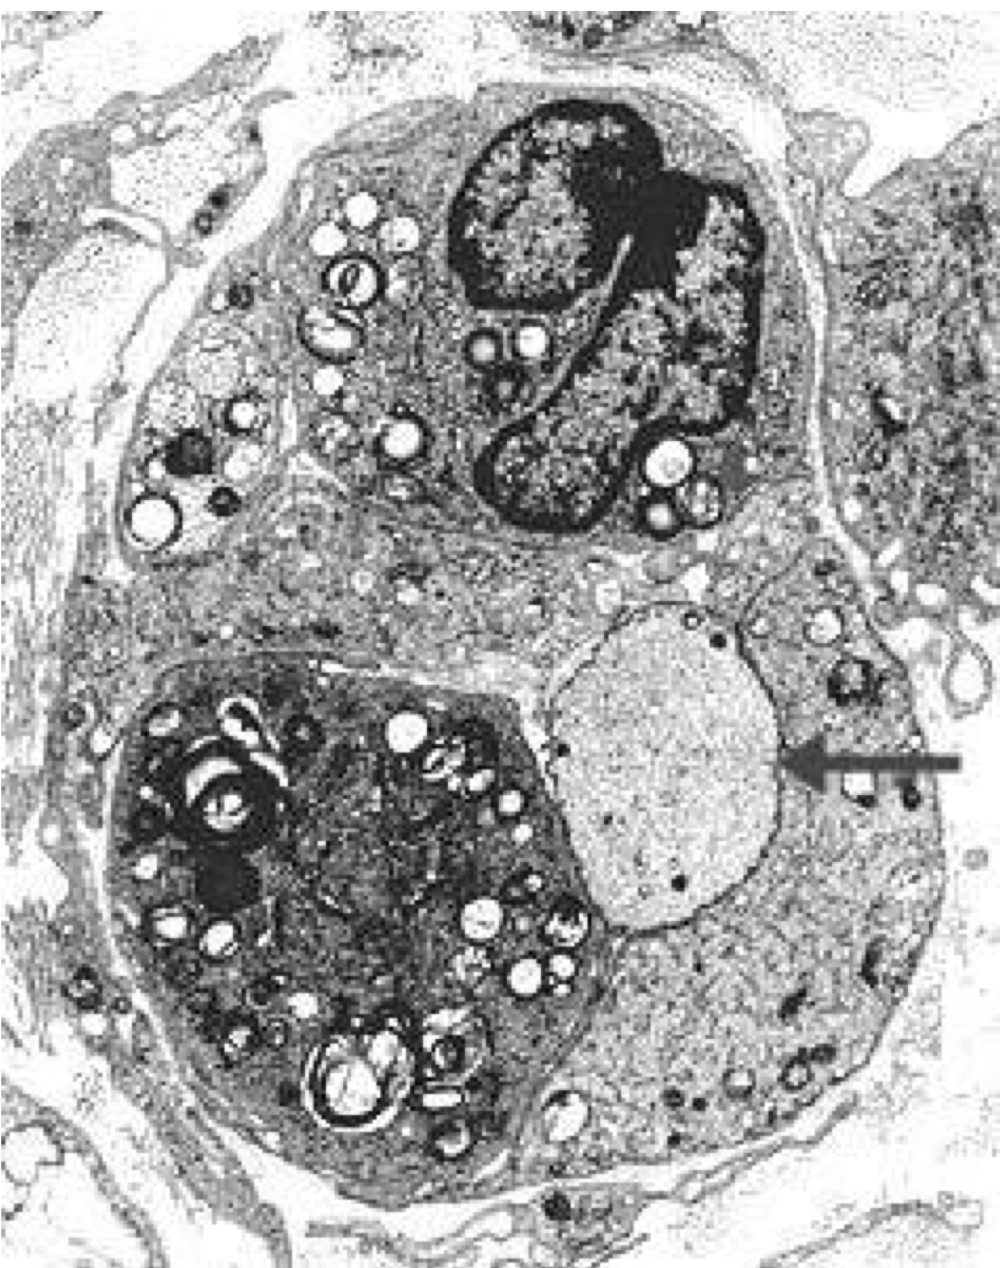

Coonhound paralysis, axonal degeneration:

loss of morphologic detail in axoplasm and abundant myelin debris

• black discoloration

• secondary myelin destruction, splitting, debris in Schwann cells and macrophages